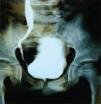

Presentación de los casosCaso 1Masculino de 12 años de edad, con antecedente de infecciones urinarias recurrentes desde los 7 meses de edad. Presenta incontinencia urinaria continua. Es manejado anteriormente con cateterismo limpio intermitente al parecer sin adecuado apego, no mostrando mejoría. Presenta una creatinina sérica de 0.7mg/dL con urea de 49mg/dL, el examen general de orina muestra: leucocituria, bacterias abundantes, nitritos positivos y proteinuria de 300 mg/dL. Presenta un cultivo positivo para Escherichia coli (E. coli) > 100,000 UFC; se indica tratamiento con antibiótico. En la cistografía se evidencia una vejiga de esfuerzo, con reflujo vesicoureteral G-5 derecho y abundante orina residual (fig. 1). El ultrasonido muestra ectasia renal derecha severa y ectasia moderada izquierda (fig. 2). La resonancia magnética de columna se encuentra normal y la valoración por Neurocirugía corrobora que no hay alteración neurológica, la cistoscopia reveló que no hay valvas uretrales. Se realiza ampliación vesical con sigmoides más estoma de Mitrofanoff, se maneja con cateterismo limpio intermitente a través del estoma. En el seguimiento presenta mejoría clínica notable a razón de cese de las infecciones, disminución de ectasia renal (fig. 3), así como desaparición del reflujo vesicoureteral (fig. 4) y continencia completa entre los cateterismos.